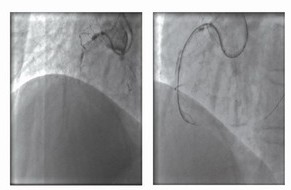

如果导引钢丝不能通过病变,而对侧侧支循环较好的情况下,可以试图经对侧侧支循环逆向通过闭塞远端通过病变,或者即使逆向导丝不能完全通过病变而通过双侧钢丝对吻技术也可完成介入治疗(图2),该方法又称为逆向钢丝对吻技术 (Retrograde wire kissing technique)。该技术通常选用直径大于1mm的侧支血管,在放置导引钢丝之前,应冠脉内给予硝酸甘油,然后选择亲水涂层导丝,小心通过侧支血管进入闭塞血管远端。必须指出的是因侧支血管血管壁较薄,导引钢丝操作不当则有可能发生血管穿孔。